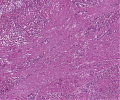

A52 Hodgkin-Lymphom

Mehrkernige Reed-Sternberg Zelle mit mit prominenten Nukleoli beim klassischen Hodgkin-Lymphom.